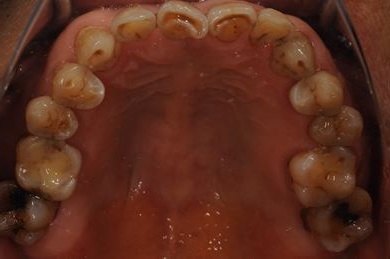

抜歯即日スピードインプラント治療+セラミック治療+歯肉遊離移植術

| 性別/年齢 | 男性 / 64歳 | ||||||||||||||||||||||||||||||||

| 治療内容 | インプラント4本(抜歯即日スピードインプラント)、メタルボンドセラミッククラウン5本、ハイブリッドセラミッククラウン1本(ハイブリッドセラミック用土台1本) | ||||||||||||||||||||||||||||||||